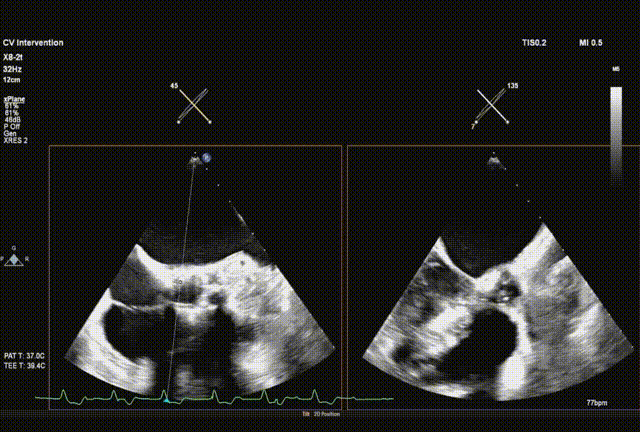

超声引导直头导丝跨瓣成功

交换送入猪尾导管并确认到达心尖

采样线扫到左室心尖并送入safari导丝

球囊预扩

输送系统顺利跨瓣

瓣膜初始释放到喇叭状形态并定位植入深度

采样线扫到无窦,180起搏,长轴视图下快速释放到工作位

超声从左至右,最后无冠窦侧评估深度合适

起搏下完全释放瓣膜

左右旋转系统并前送,观察无瓣膜移动,回撤导丝后再撤出系统

术后超声评估,未见瓣周漏,平均跨瓣压15 mmHg,血流速度197 cm/s